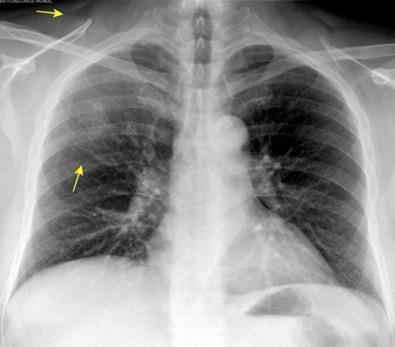

Carcinoma de mama izquierda

Nódulo en língula.

Cirugía de Ca .de mama hace 23 añosedema de brazo y ganglio en axila. ¡Metástasis!.

Ecanow JS et l. Axillary Staging of Breast Cancer: What the Radiologist Should Know. Radiographics 2013